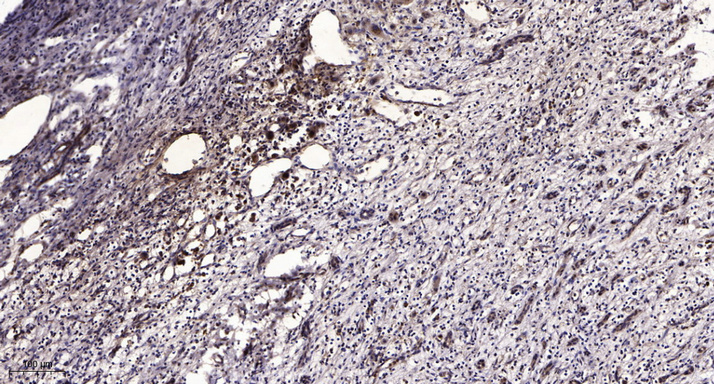

WB, IHC, IF, IP

Optimal working dilutions should be determined experimentally by the investigator; Suggested starting dilutions are as follows:IHC 1:50-300; IF 1:200.